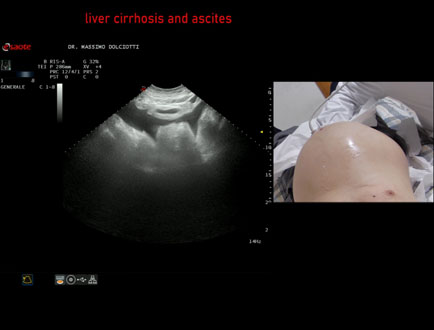

Data inserimento: 08/04/2015

Ecografia del: 27/03/2015

Strumento: Esaote MyLab 50 Gold - Responsabile Linea Cardio Esaote Regione Marche Dr. Franco Fabi

Sonda: Convex Multifrequenza 2,5-6,6 Mhz

Età Paziente: M 69 anni

Motivazione dell'esame: incremento del volume dell'addome, astenia intensa e dispnea. Abuso etilico.

Commento all'esame: le immagini ed il video documentano il fegato ridotto di dimensioni, con profilo irregolare, abbondante ascite, milza normale, rene destro con piccola cisti, pancreas normale.

Conclusioni: cirrosi epatica alcolica scompensata con abbondante ascite (decompensated alcoholic liver cirrhosis with abundant ascites).